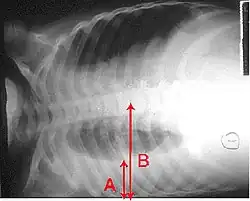

Imagistica

Radiografia toracică este frecvent utilizată în stabilirea unui diagnostic.[14] La persoanele cu forme mai ușoare, radiografia este necesară numai în cazul celor cu posibile complicații, celor care nu răspund la tratament, sau atunci când cauza este incertă.[14][41] Dacă o persoană este atât de bolnavă încât necesită spitalizarea, se recomandă o radiografie toracică.[41] Rezultatele nu indică întotdeauna severitatea bolii și nu deosebesc cu siguranță între infecțiile bacteriene și cele virale.[14]

Radiografiile pot clasifica pneumonia drept pneumonie lobară, bronhopneumonie (cunoscută drept pneumonie lobulară), și pneumonie interstițială.[44] Pneumonia bacteriană, existentă în comunitate, prezintă de regulă consolidarea pulmonară a unui lob pulmonar, fiind cunoscută drept pneumonie lobară.[24] Cu toate acestea, rezultatele pot varia, iar alte caracteristici sunt obișnuite în alte tipuri de pneumonie.[24] Pneumonia de aspirație poate prezenta opacități bilaterale mai ales la baza plămânilor și pe partea dreaptă.[24] Este posibil ca în unele cazuri radiografiile pneumoniei virale să pară normale, să aibă un aspect hiper-inflamat sau să pară similare pneumoniei bacteriene cu consolidare lobară.[24] Este posibil ca în stadiile incipiente ale bolii să nu existe semne depistabile radiologic, mai ales în cazul deshidratării; sau pot fi dificil de interpretat în cazul persoanelor obeze sau care au antecedente de afecțiuni pulmonare.[15] O tomografie computerizată poate oferi informații suplimentare în cazurile incerte.[24]